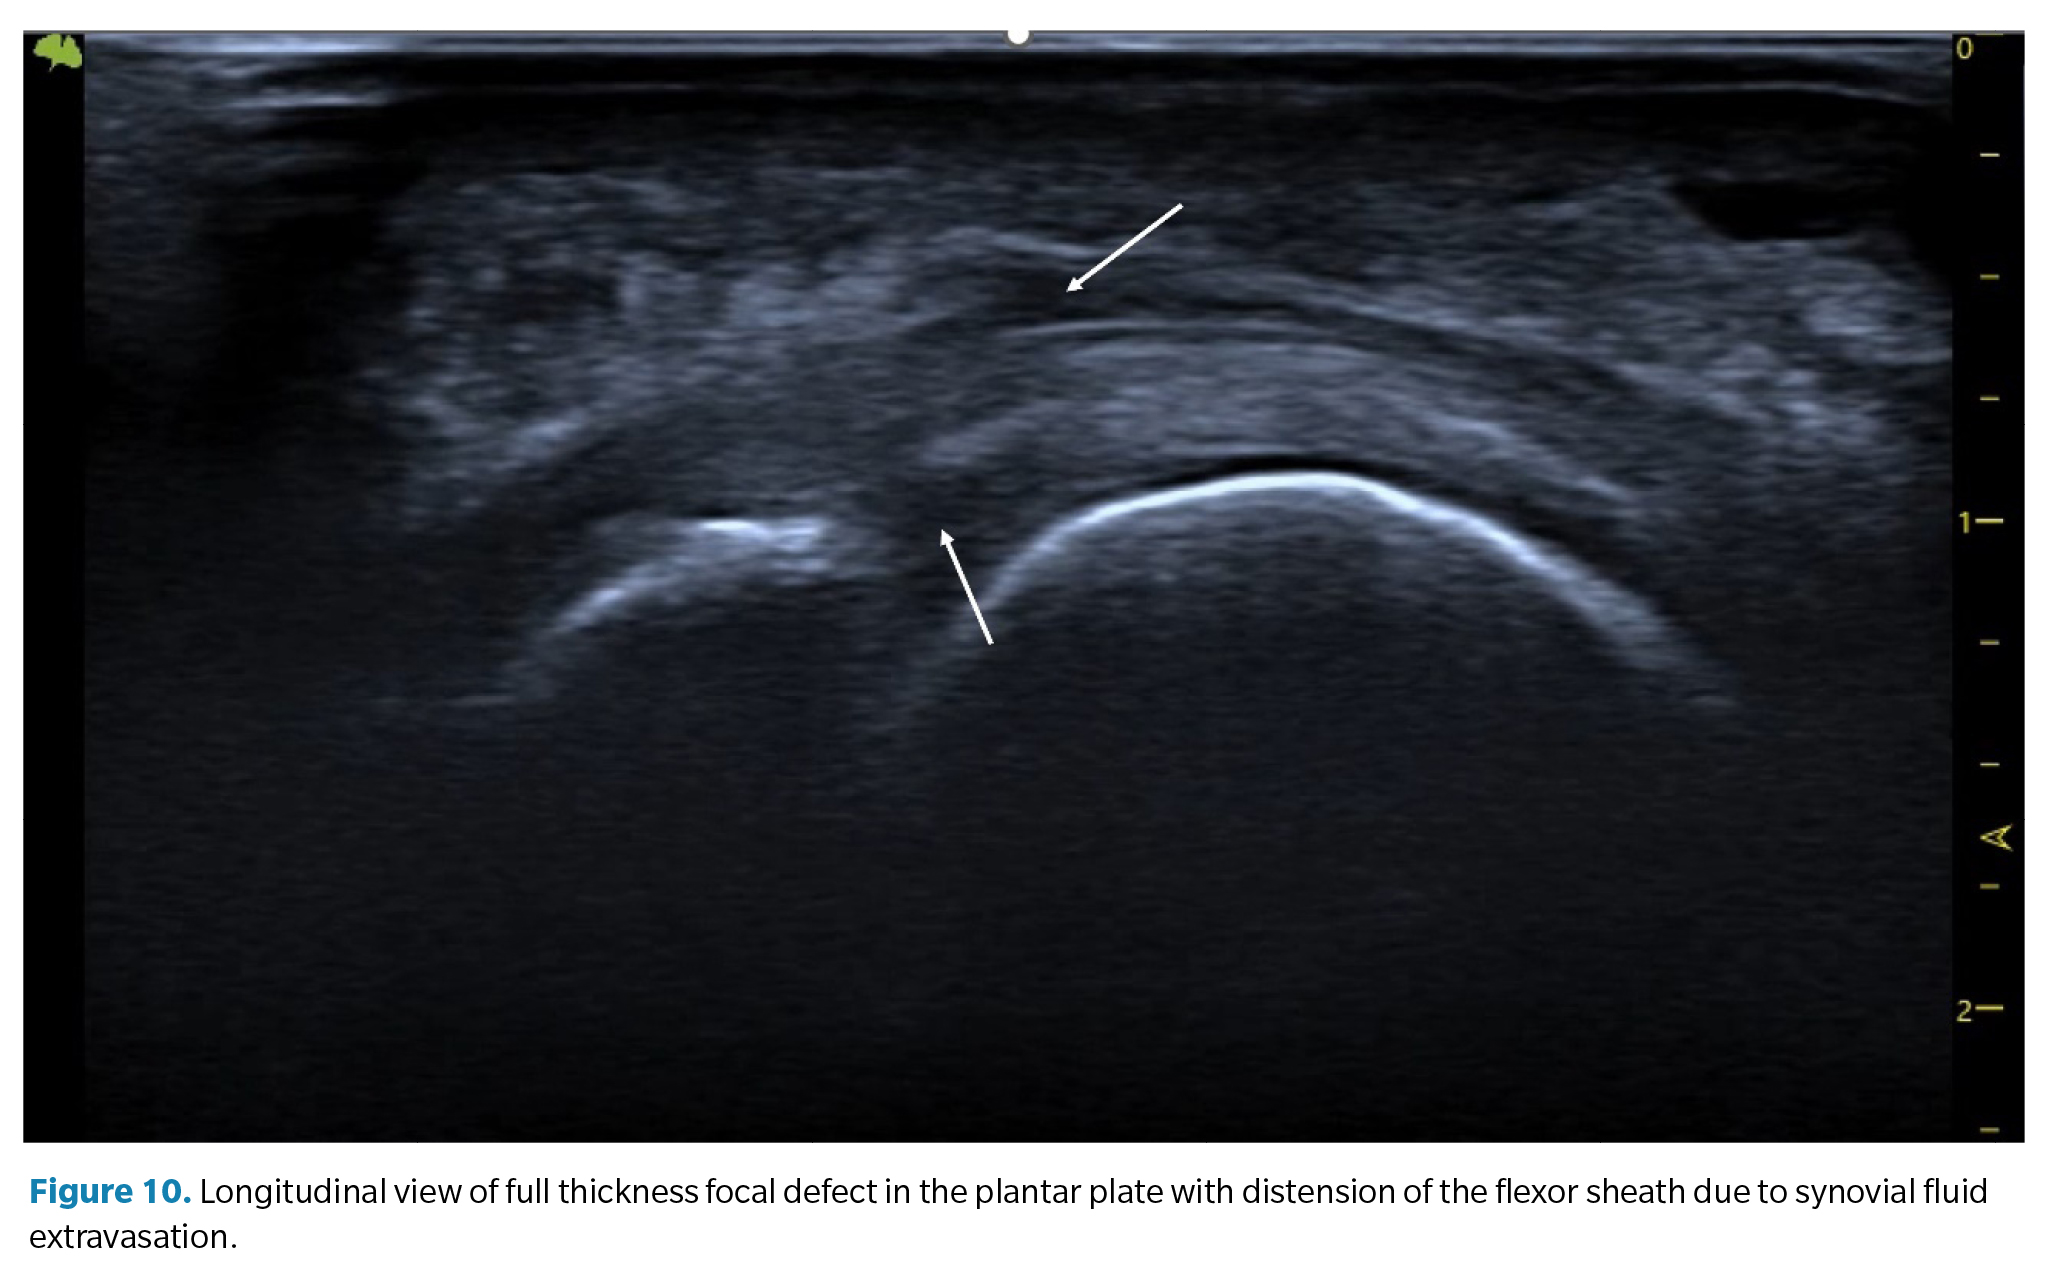

1. Anechoic or hypoechoic focal defect. They appear as a discrete cleft in the deep tissue area (the area that articulates with the metatarsal head) on its lateral margin. When the superficial fibers are intact, it is called a partial-thickness tear, while a tear that traverses the entire tissue to its superficial region is called a full-thickness tear(39) (Figure 8).

1. Plantar or dorsal joint fluid (synovitis). Synovial effusion. Since the plantar plate forms the plantar closure of the joint capsule, tears in the plate can lead to a significant increase in synovial fluid, which manifests as a detectable synovial effusion both dorsally and plantarly. In some cases, this fluid can leak into the flexor tendons, creating a hypoechoic halo around them resembling the characteristic image of tenosynovitis with distension of the tendon sheath (Figure 10).